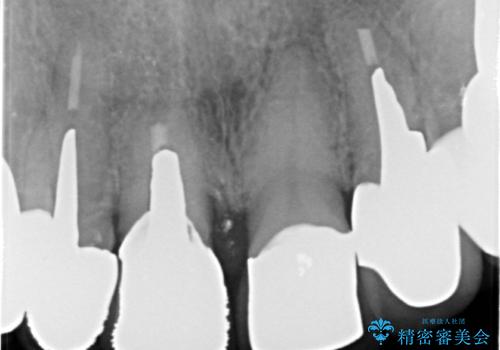

10数年前に治療を行った保険適応の硬質レジン前装冠は変色劣化が進み、審美的に問題があるだけでなく虫歯のリスクも高くなり好ましくない状況です。

審美的かつ精度の高いセラミック治療を行うことで、汚れがつきにくく虫歯や歯周病の感染リスクを将来にわたって抑える治療が可能になります。